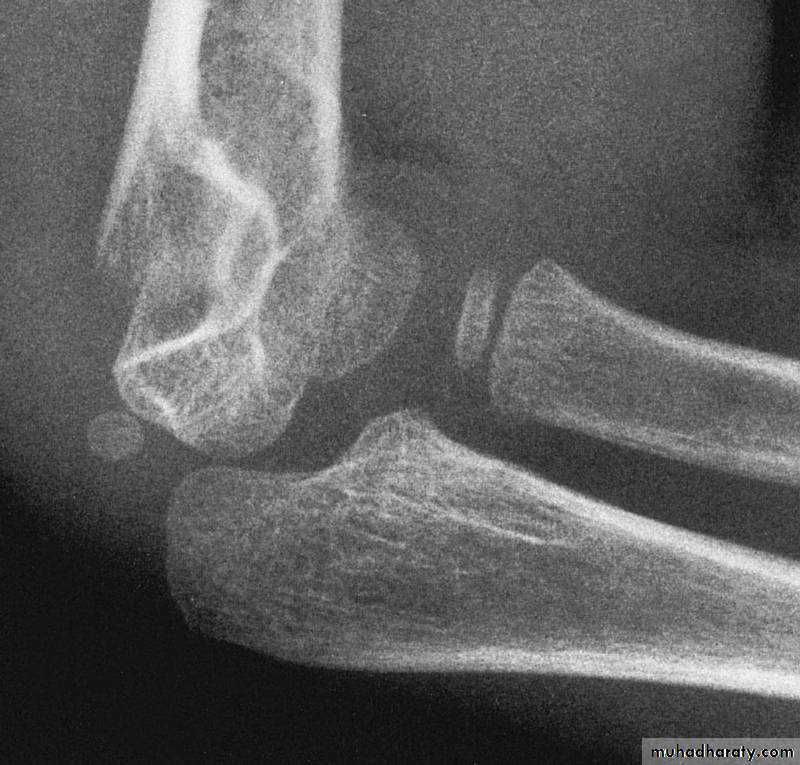

What type of supracondylar fracture

does this patient have?Flex

ionHow do the flexion patterns present?

This classical Type III pattern

is obviously a flexion injury.With these one needs to be

prepared to do an open reduction !!

8 y.o.

Is this a simple extension

type supracondylar fracture ??

It also has

anterolatateraldisplacement !!

The distal fragment is

not flexed,but also it is not extended to any degree.

This also is a Type III Flexion Pattern.

What is differentabout this fracture?

But, if not recognized as such, it may be a problem.

This fracture was irreducible,

and required an open reduction !!!